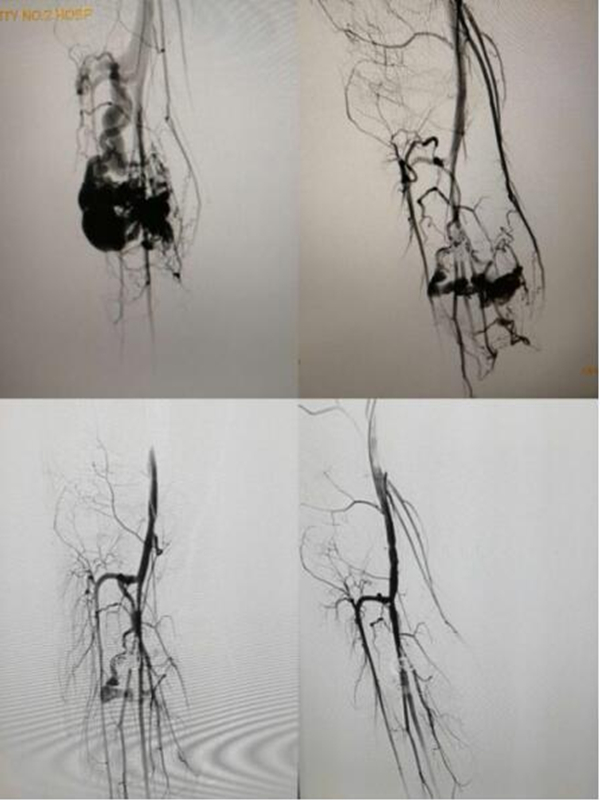

刚步入七月,小儿外科住院病人骤增,高峰期并一直持续到九月初。住院量在往年高住院量上再创历史新高,一个病区40张床,其中七月份出院298人,比去年增长15%,八月份出院289人,比去年增长12%。诊治患儿中除了大量疝气、鞘膜积液、隐睾、隐匿性阴茎的中小学生和借暑假来做血管畸形介入的高中、大学生外,今年疑难、危重急诊和新生儿的患儿比例也比往年明显增加。其中吴宣林副教授、龚伟医生一周手术量达40多例,是全科手术例数最多;李鹏教授、潘伟康副教授在整个假期三、四大手术和复杂新生儿畸形不可枚举;郭新奎副教授、王怀杰医生介入经常做到午夜......